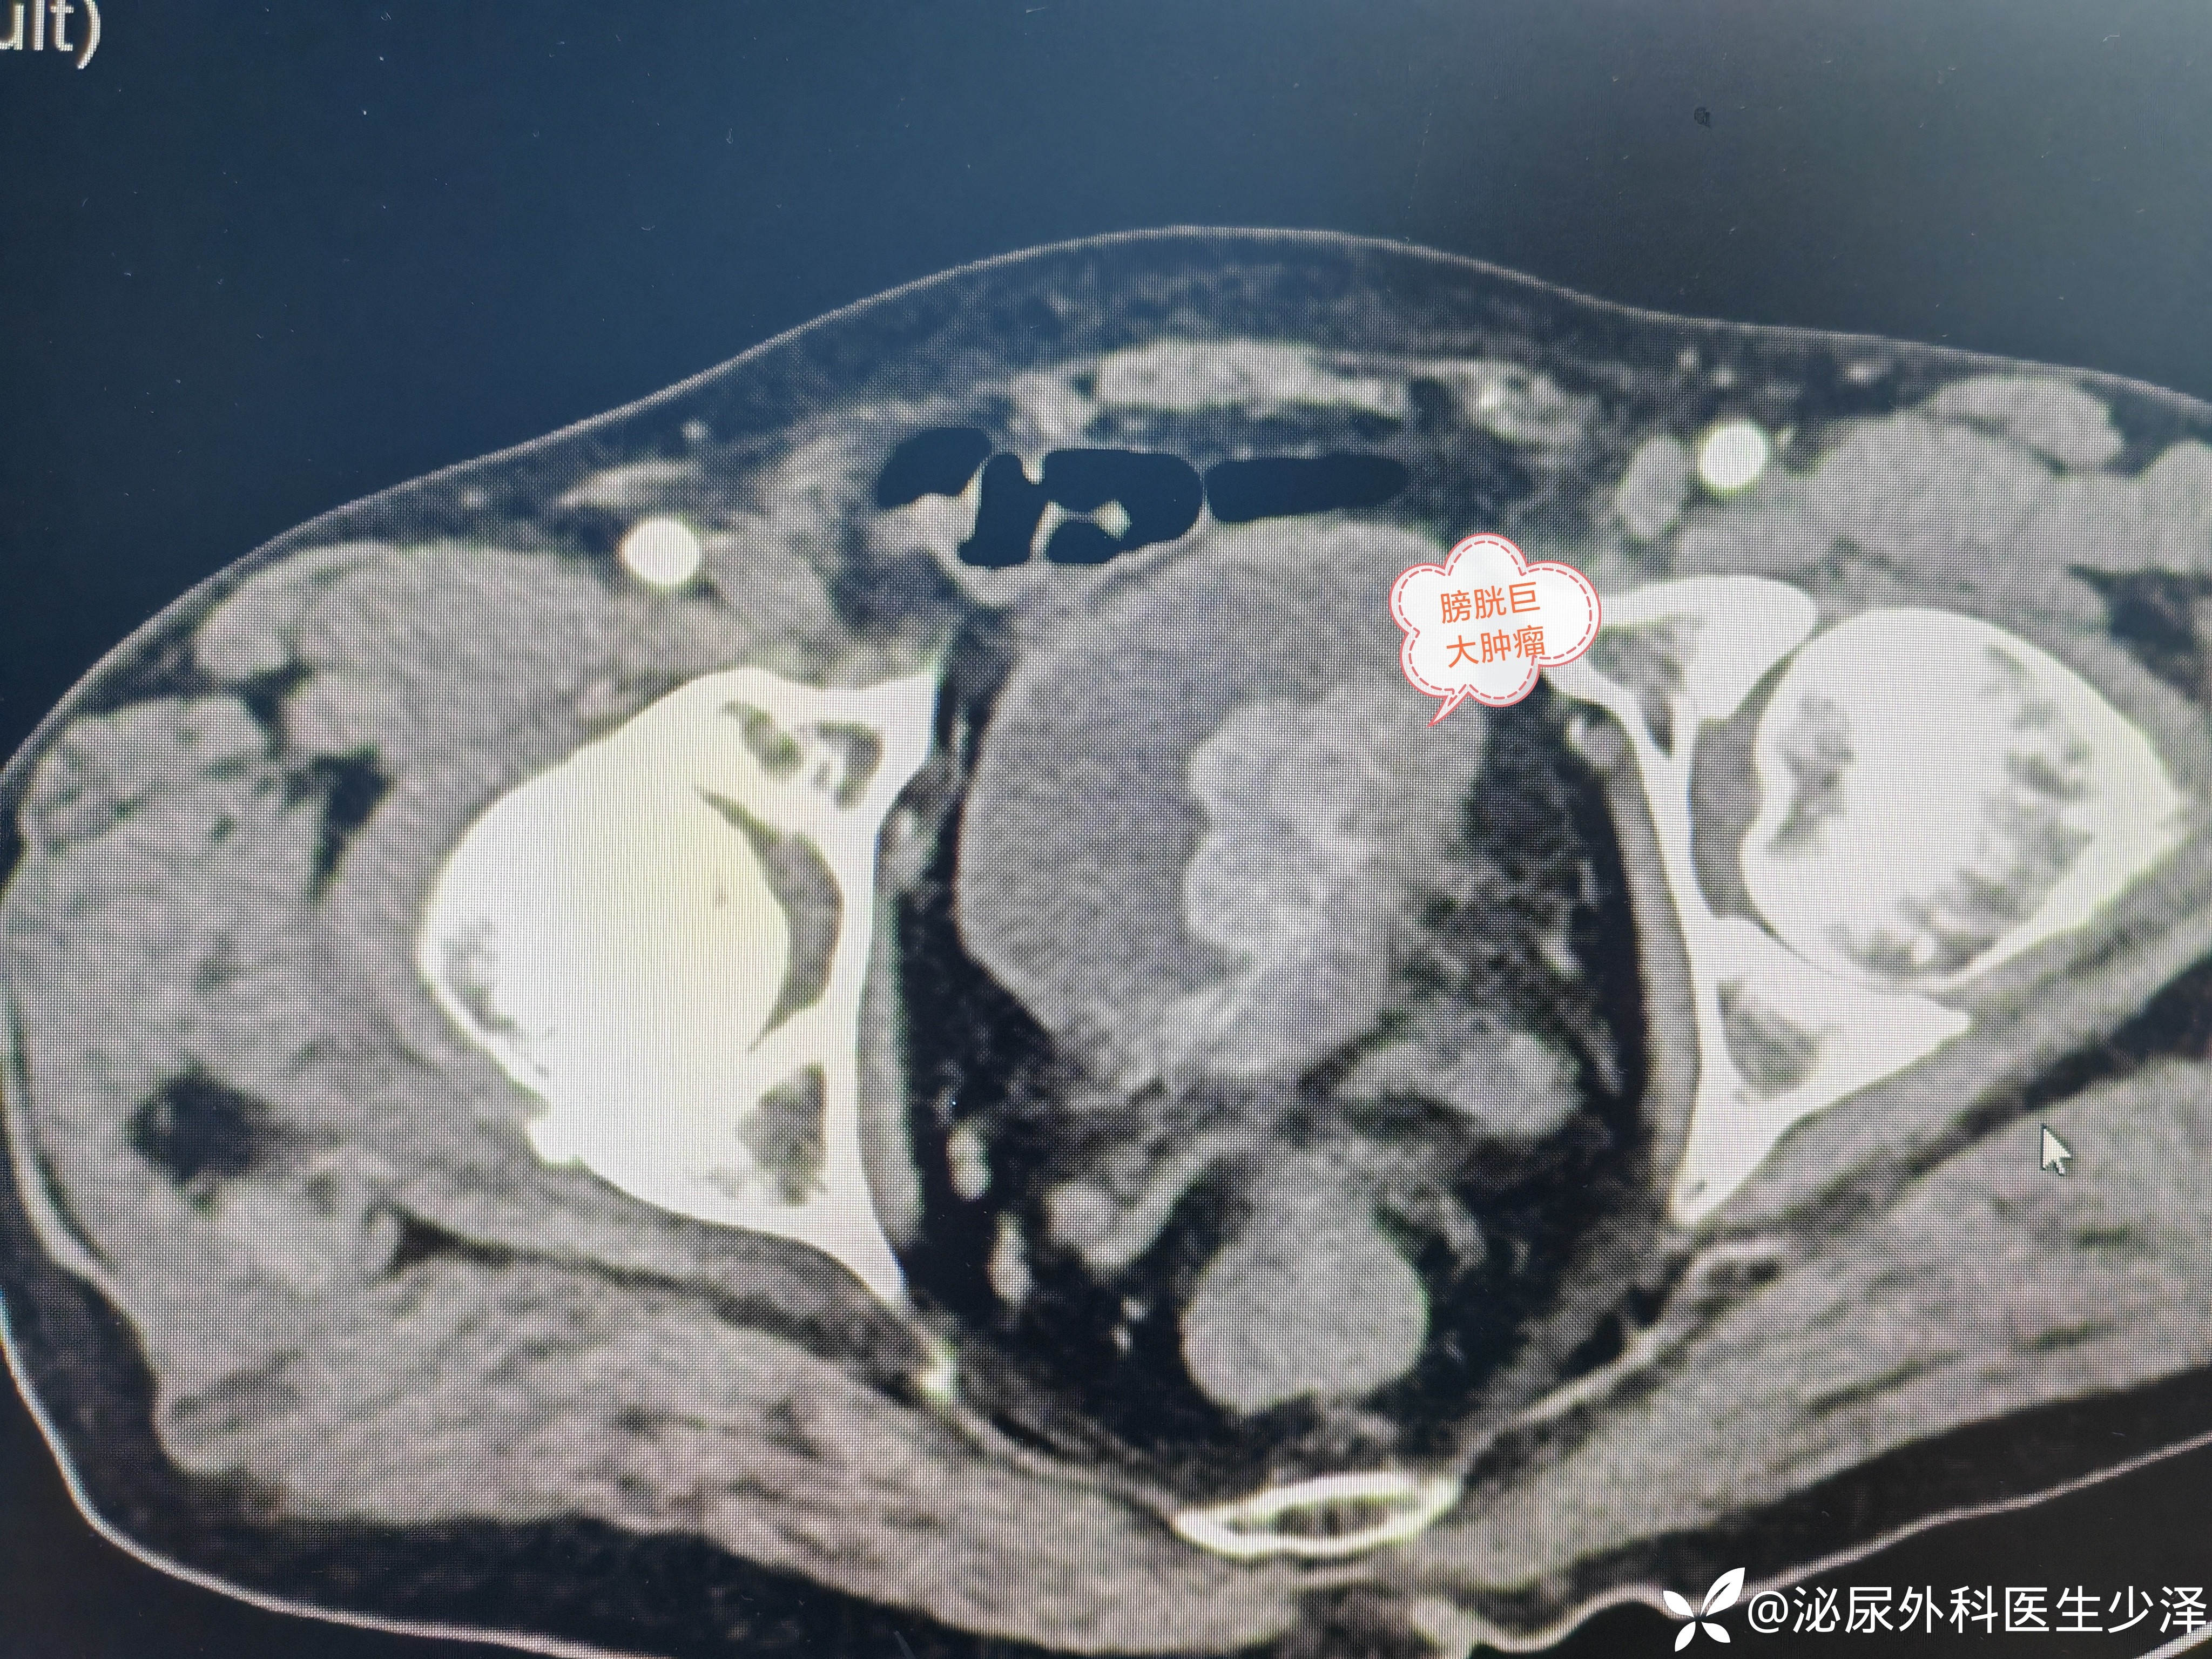

今日下午,完成一例腹腔镜下根治性膀胱全切+盆腔淋巴清扫+双侧输尿管造口术,72岁患者反复无痛性肉眼血尿,手术顺利,历时4小时。感谢张晓明、王琪的默契配合。医者之路,步步不易,但每一步都算数。